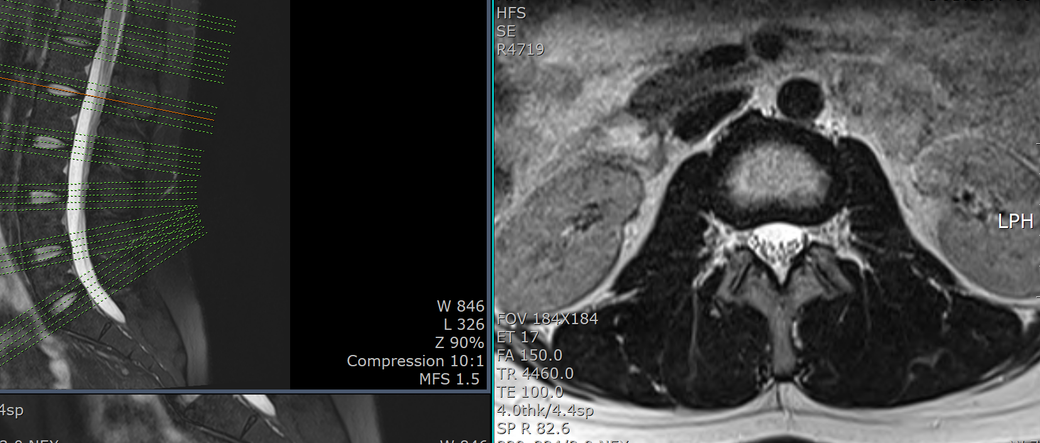

mri 판독 결과 남깁니다..

T12-L1 level에서 disc가 뒤쪽 Lt. central aspect로 protrusion되어 있고 mild한 dural sac indentation을 주고 있음.

그 외 disc level과 neural foramen에서 definite한 abnormality는 보이지 않음.

• 3번 째 사진

아래 사진에 있는 부위가 아마 T12/L1 사이에 디스크가 살짝 뒤로 빠져있다는 부위이실겁니다.

우선은 이 디스크 내장증으로 인한 연관통으로 보고 요추전만 자세를 잘 실천해보시는게 가장 우선 필요한 조치이겠습니다.

수술을 주로 다루는 신경외과, 정형외과 선생님들의 경우에 심한 디스크탈출 및 신경뿌리를 누르는 신경뿌리병증이 생길만한 병변만 통증을 유발한다고 보시기 때문에 문제될만한 병변이 없다고 이야기 하셨을텐데 저렇게 작게 찢어진 디스크 때문에도 충분히 통증이 생길 수 있습니다. 물론 찢어진 디스크의 위치에 비해 통증이 밑에 있는 편이시지만 이게 불가능한건 아닙니다. 디스크 내장증이라고 하며 이럴때는 요추전만 자세가 가장 중요합니다.

피부가 찢어지면 봉합을 하듯이 찢어진 부위가 아물도록 상처를 오므려놓는게 필요한데 이게 바로 요추전만 자세의 유지입니다.

허리를 하루에 한번도 안굽힌다고 생각하고 생활해보시기 바랍니다.